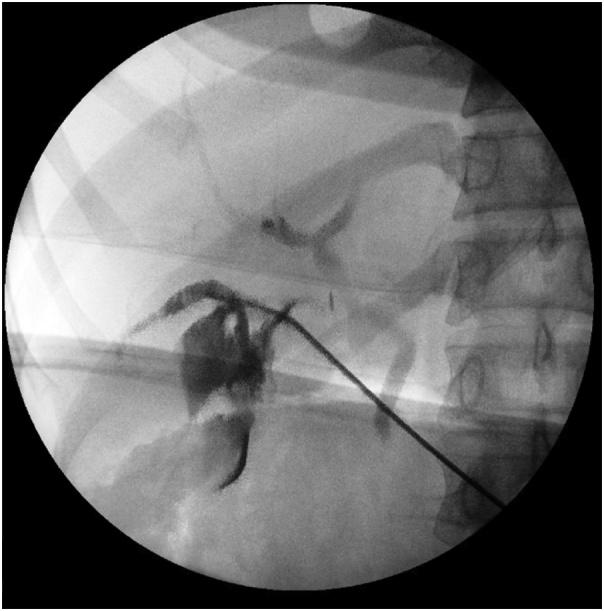

A 34-year-old female presented with signs and symptoms of acute cholecystitis which was confirmed on imaging. She was found to have an accessory cystic duct on laparoscopic cholecystectomy requiring conversion to open laparotomy with intraoperative cholangiogram to delineate the anatomy.

一名34岁女性出现急性胆囊炎的体征和症状,影像学检查得以证实。在腹腔镜胆囊切除术中发现她有一条副胆囊管,需要转为开腹手术并进行术中胆管造影以明确解剖结构。

The limited success of preoperative biliary tract imaging in demonstrating anatomic aberrancies prior to cholecystectomy clearly highlights the importance of maintaining constant vigilance for even the slightest anatomic abnormality at operation. Any uncertainty or concern for ductal injury mandates immediate operative cholangiogram with cannulation of all structures in question.

术前胆道成像在胆囊切除术前显示解剖异常方面取得的成功有限,这清楚地凸显了术中对哪怕最轻微的解剖异常保持持续警惕的重要性。任何对导管损伤的不确定或担忧都要求立即进行术中胆管造影,并对所有相关结构进行插管。